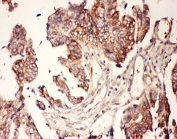

IHC-P: CNTF antibody testing of human lung cancer tissue. HIER: steamed with pH6 citrate buffer.